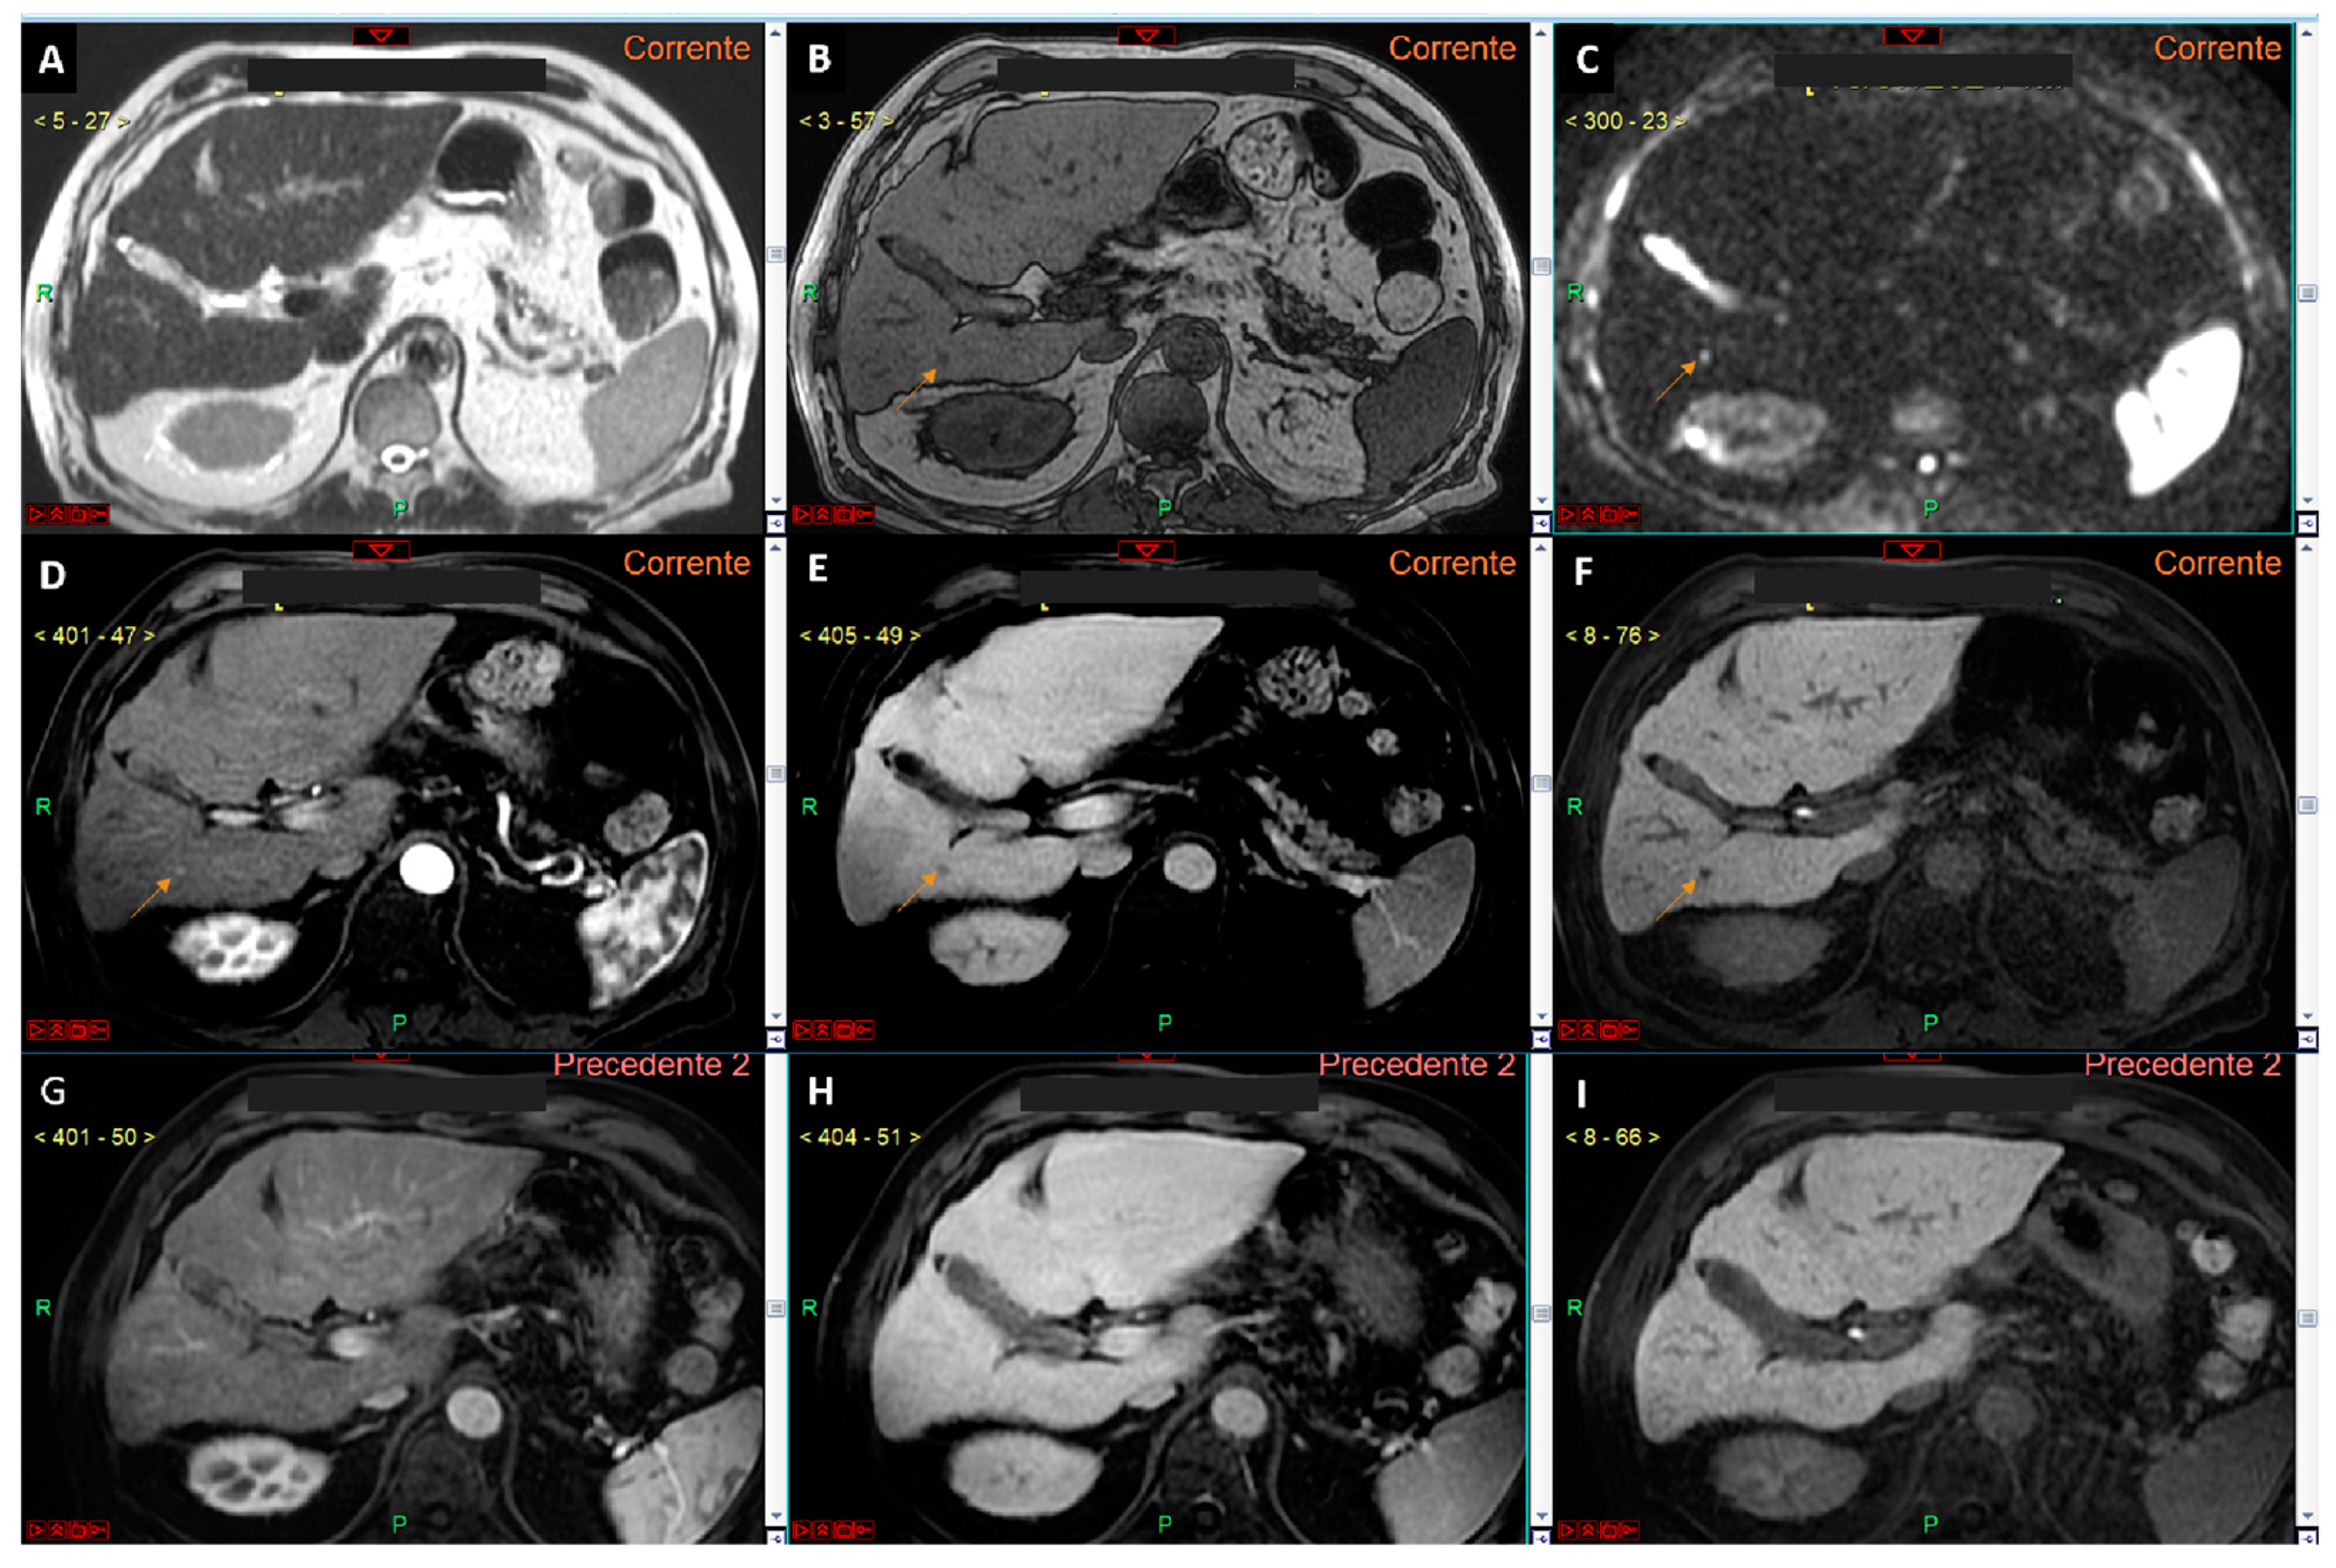

- Renzulli, M.; Biselli, M.; Brocchi, S.; Granito, A.; Vasuri, F.; Tovoli, F.; Sessagesimi, E.; Piscaglia, F.; D’Errico, A.; Bolondi, L.; et al. New hallmark of hepatocellular carcinoma, early hepatocellular carcinoma and high-grade dysplastic nodules on Gd-EOB-DTPA MRI in patients with cirrhosis: A new diagnostic algorithm. Gut 2018, 67, 1674–1682. [Google Scholar] [CrossRef]

- Renzulli, M.; Golfieri, R.; Bologna Liver Oncology Group (BLOG). Proposal of a new diagnostic algorithm for hepatocellular carcinoma based on the Japanese guidelines but adapted to the Western world for patients under surveillance for chronic liver disease. J. Gastroenterol. Hepatol. 2016, 31, 69–80. [Google Scholar] [CrossRef] [PubMed]